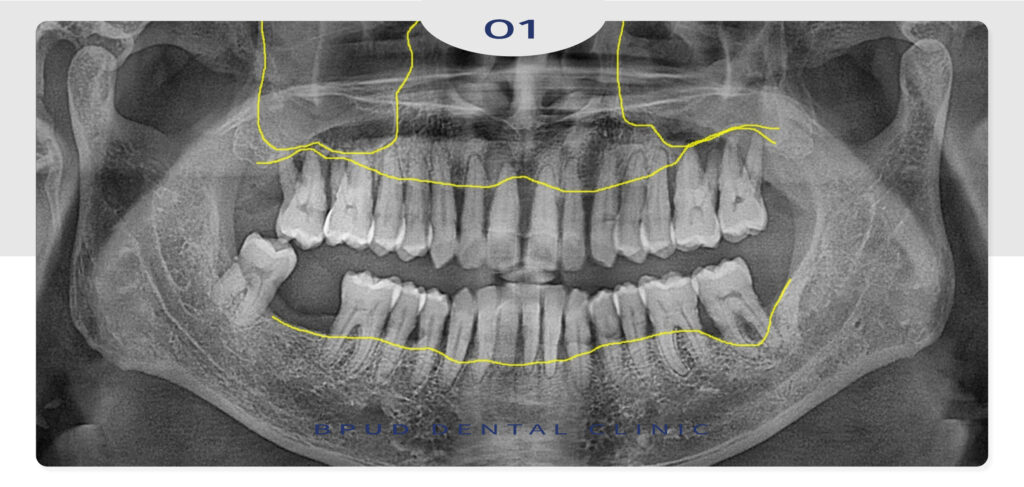

상악동 거상술은 위턱의 어금니 부위에 위치한

상악동 점막을 위로 들어 올리고, 그 아래 공간에

뼈 이식재를 삽입해 인공치근이 고정될 수 있는

충분한 골량을 확보하는 수술을 말하는데요.

잇몸뼈가 4~5mm 이하로 얇거나 아래로 많이

확장되어 있는 경우에는 이 수술을 통해

안정적인 식립 기반을 만들어주는 것이 중요합니다.

이 시술은 임플란트 식립 전 혹은 식립과 동시에

병행될 수 있으며 그 결정은 잇몸뼈의 상태,

환자의 전신 건강, 시술 부위의 해부학적 조건 등을

종합적으로 고려해 이루어져야 하며

시술 전에는 CT를 통한 정밀 진단을 선행하여

상악동 내부 해부학적 구조나 점막의 두께,

뼈의 높이 등 다양한 요소가 정밀하게 진단되어야 합니다.